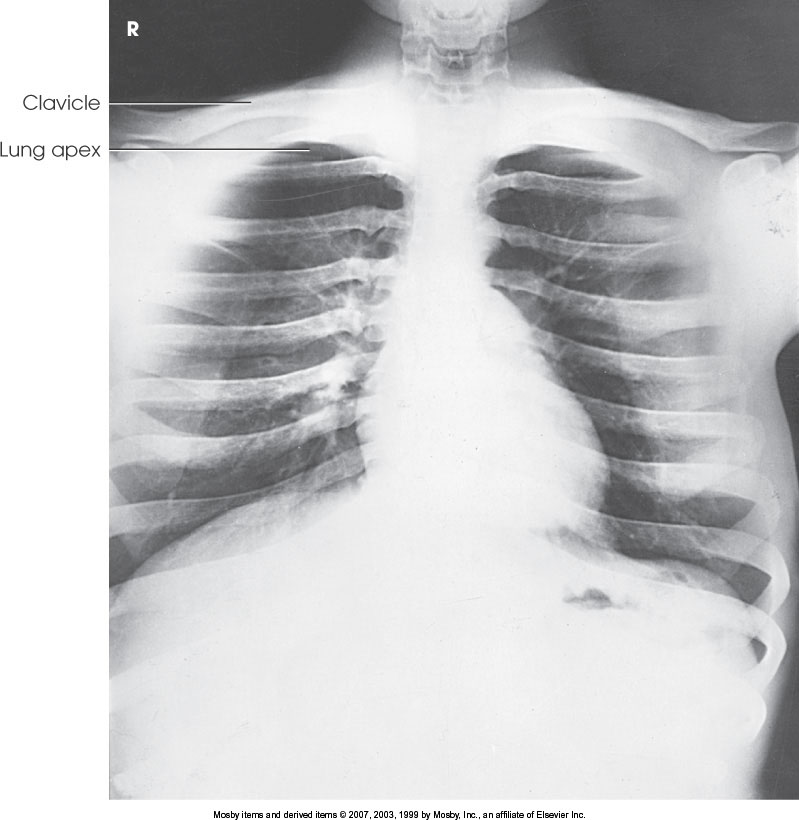

What position is demonstrated?

Right Lateral Decubitus Chest